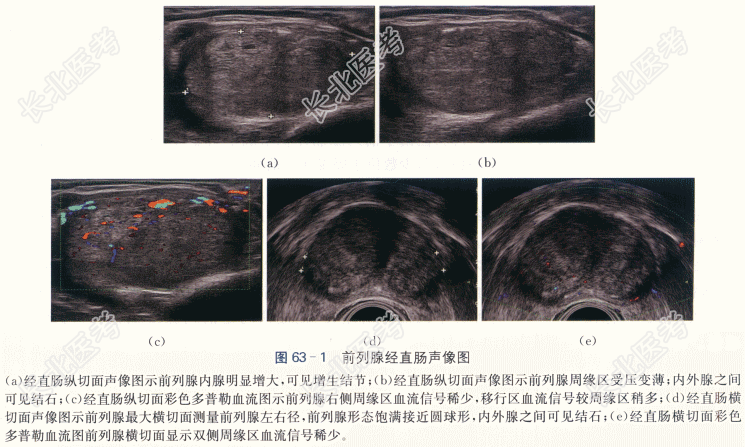

患者,男性,70岁,因“排尿不畅10年余,发现前列腺特异抗原(PSA)升高3月”就诊。患者10年前无明显诱因下出现排尿踌躇,费力,无发热,无尿频、尿急、尿痛,夜尿2~3次/天,尿液颜色正常。3月前体检发现PSA值10.07ng/ml,遂来我院就诊。

患者双肾无叩击痛,双侧输尿管移行区无压痛,耻骨上膀胱区无膨胀,无压痛,直肠指检示前列腺体积增大,表面光滑,质韧,边缘清楚,中央沟变浅,未扪及明显硬结。

PSA10.07ng/ml,fPSA3.98ng/ml,fPSA/PSA0.39。尿常规(-),血常规(-)。